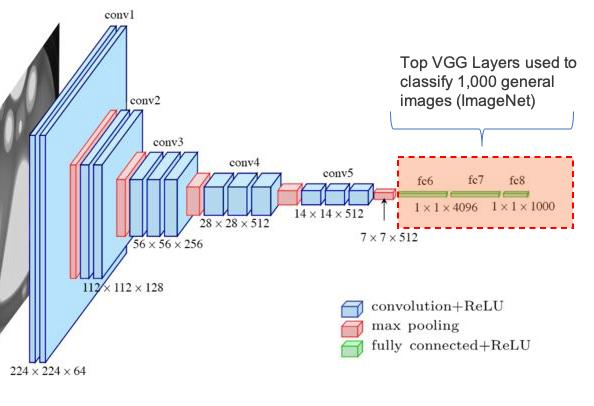

使用的预训练模型是VGG16,由牛津大学视觉图形组(VGG)开发,并在论文“Very Deep Convolutional Networks for Large-Scale Image Recognition”中描述。除了在开发公共的图像分类模型时非常流行外,这也是Adrian博士在其教程中建议的模型。

理想的做法是使用几个模型(例如ResNet50v2、ResNet101v2)进行测试(基准测试),甚至创建一个特定的模型(如Zhang等人在论文中建议的模型:https://arxiv.org/pdf/2003.12338.pdf),但由于这项工作的最终目标只是概念上的验证,所以我们仅探索VGG16。

VGG16是一种卷积神经网络(CNN)体系结构,尽管在2014年已经开发出来,但今天仍然被认为是处理图像分类的最佳体系结构之一。

VGG16体系结构的一个特点是,它们没有大量的超参数,而是专注于卷积层上,卷积层上有一个3x3滤波器(核)和一个2x2最大池层。在整个体系结构中始终保持一组卷积和最大池化层,最后该架构有2个FC(完全连接的层)和softmax激活输出。

VGG16中的16表示架构中有16个带权重的层。该网络是巨大的,在使用所有原始16层的情况下,有将近1.4亿个训练参数。

在我们的例子中,最后两层(FC1和FC2)是在本地训练的,参数总数超过1500万,其中大约有590000个参数是在本地训练的(而其余的是“frozen(冻结的)”)。

需要注意的第一点是,VNN16架构的第一层使用224x224x3的图像,因此我们必须确保要训练的X光图像也具有这些维度,因为它们是卷积网络的“第一层”的一部分,因此当使用原始权重(weights=“imagenet”)加载模型时,我们不保留模型的顶层(include_top=False),而这些层将被我们的层(headModel)替换。

baseModel = VGG16(weights="imagenet", include_top=False, input_tensor=Input(shape=(224, 224, 3)))